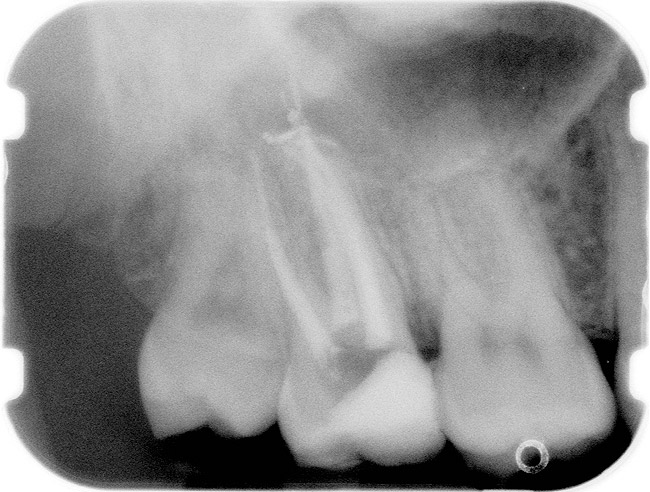

Figure 1  X-ray of an endodontically treated second bicuspid restored with a fiber post, core, and all-porcelain crown.

Figure 1

Case 1

A Class IN maxillary bicuspid was previously restored with a fiber post and an all-porcelain crown (Figure 1). The forces of the oral environment resulted in fracture of the fiber post and crown failure. The remaining fiber post in the root was removed, and anti-rotational areas were prepared for a cast post (Figure 2). A gold cast post was constructed at a dental laboratory, using an indirect technique (Figure 3). A porcelain-fused-to-metal (PFM) crown was constructed with a bevel finish to provide a ferrule and reduce forces on the post (Figure 4 and Figure 5).